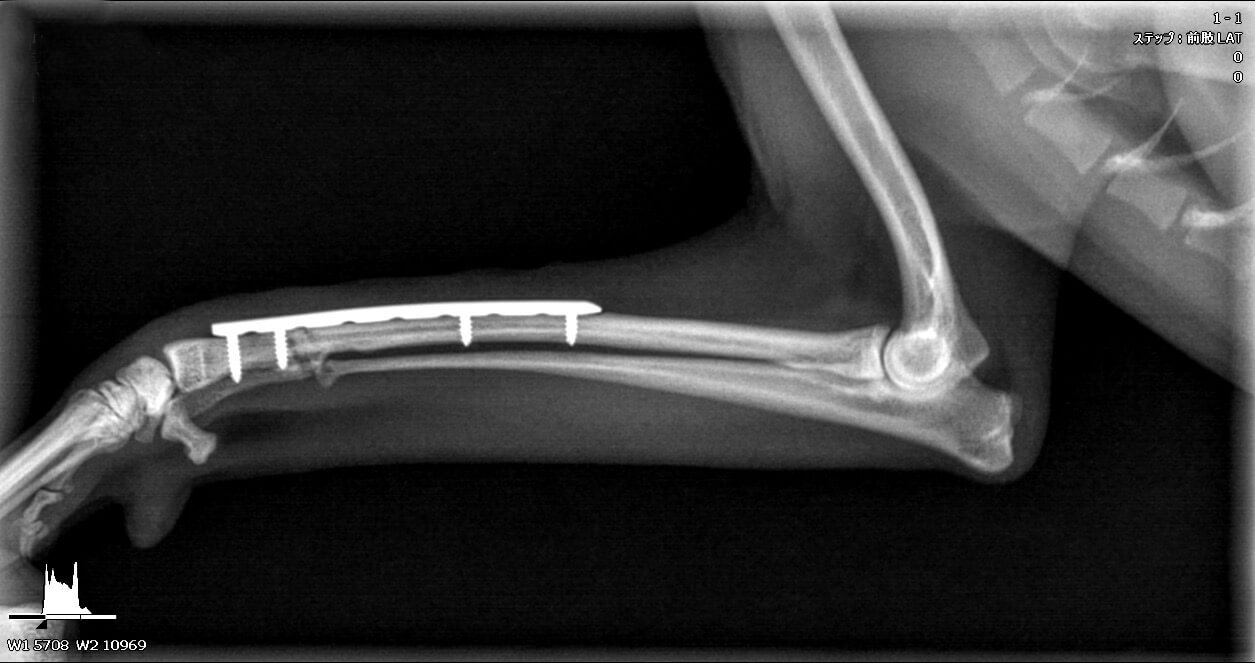

• 整形外科・内科

年を重ねても、元気に歩ける日常を。

骨折や膝蓋骨脱臼、前十字靭帯断裂などの外科疾患に加え、関節疾患や慢性的な痛みの管理、リハビリテーション、生活習慣のサポートまで幅広く対応しています。

高度な手術が必要な場合には専門の先生を招き、より適切な治療を行える体制を整えています。また、内科的な治療や継続的なケアによって生活の質を高められる場合も多くあります。特に関節や神経の病気は「治ったら終わり」ではなく、定期的な診察やケアが欠かせません。

私たちは、慢性的な痛みや加齢に伴う変化にもしっかり向き合い、ご家族と共に一歩一歩を支えます。動物たちが年を重ねても元気に歩き続けられるよう、手術からリハビリ、日常のケアまで丁寧にサポートしてまいります。